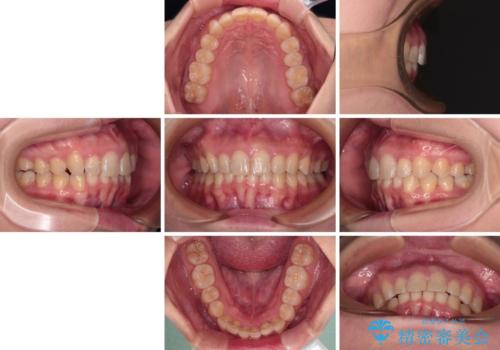

- 上の前歯の出っ歯と前歯の深い咬み合わせを治したいとのことで来院された患者様です。

上顎の歯は後方移動とIPR(歯と歯の間を削る)によって口元が引っ込むように、下顎は歯列全体の拡大とIPRによって上顎とバランスよく咬み合うように設計し、インビザラインにより治療を行うこととしました。

上顎歯列の後方への移動量が多く、右側の奥歯の咬み合わせを改善する必要もあったため、治療には長期間を要しました。